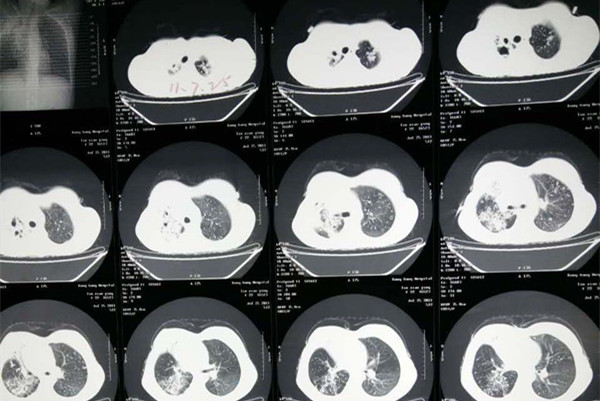

结核性胸膜炎是常见的胸膜疾病,其在各种胸膜炎中占首位,是结核杆菌及其自溶产物、代谢产物进入人超敏机体的胸膜腔而引起的胸膜炎症。目前临床根据其症状又分为干性胸膜炎、渗出性胸膜炎、结核性脓胸三种。